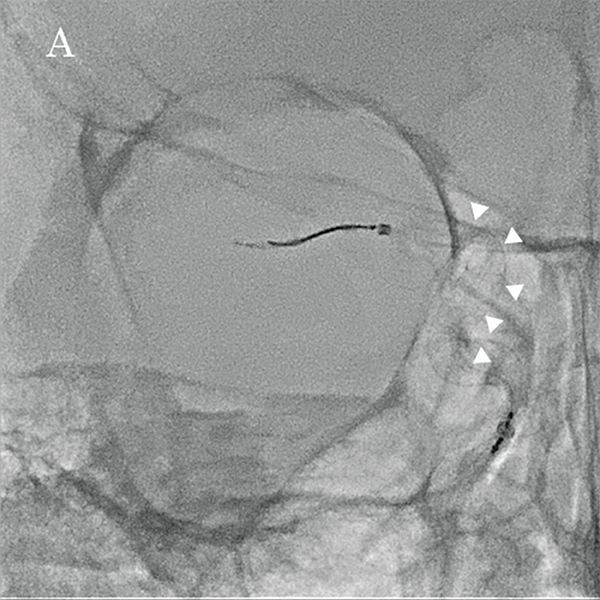

На основі цих вимірювань було обрано пристрій для емболізації Pipeline™ (PED) (4,75 мм × 16 мм; Medtronic, Японія), аневризму лікували, спостерігаючи за флюорографічними зображеннями детектора високої чіткості (мал. 5A та 5B). Пристрій було розгорнуто від C2 (біфуркація задньої сполучної артерії) до C4, а розгортання FD і стан кримпування материнської судини підтверджено Alpha CT (мал. 6A і 6B).

Малюнок 5A: Фронтальне флюороскопічне зображення, отримане за допомогою детектора високої чіткості (3 дюйми) під час розміщення FD